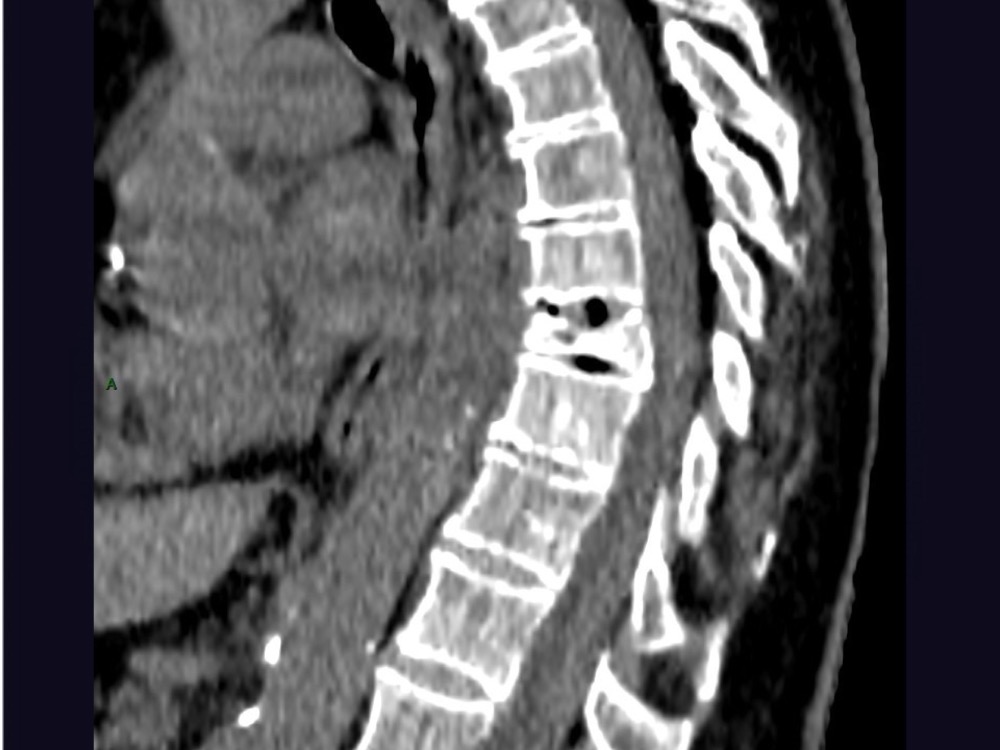

Aboudaram / Thiry 22/06/2020